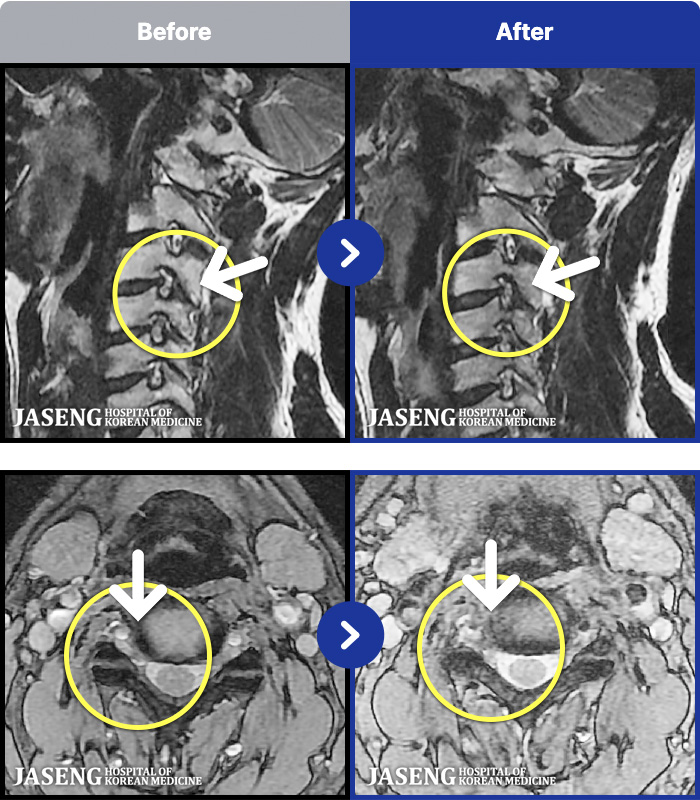

54 MRI ũ ʸ Ȯϼ.

[ϻ] 24.07.25~25.08.01